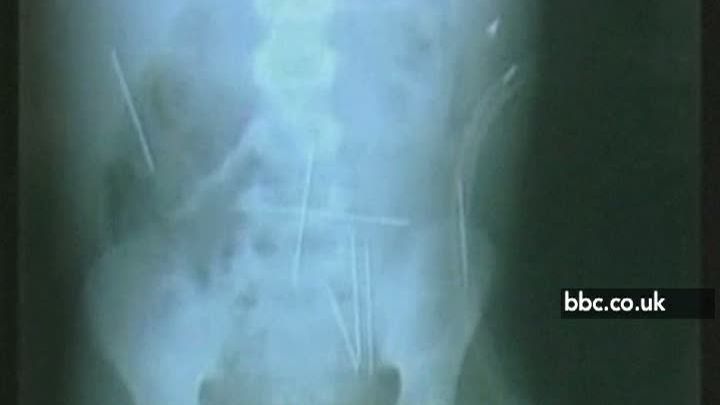

17 dec. 2009, 10:15Ultimele StiriBrazilia: Un copil, victimă a magiei negre, trăieşte cu 40 de ace înfipte în corp